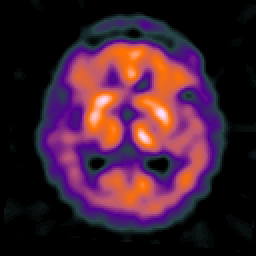

Alzheimer's disease: overlay -- Slice #13

[Home][Help][Clinical] Slice 13

Click on sagittal image to select slice. Click on thin tickmark to change timepoint, or thick tickmark for overlay.